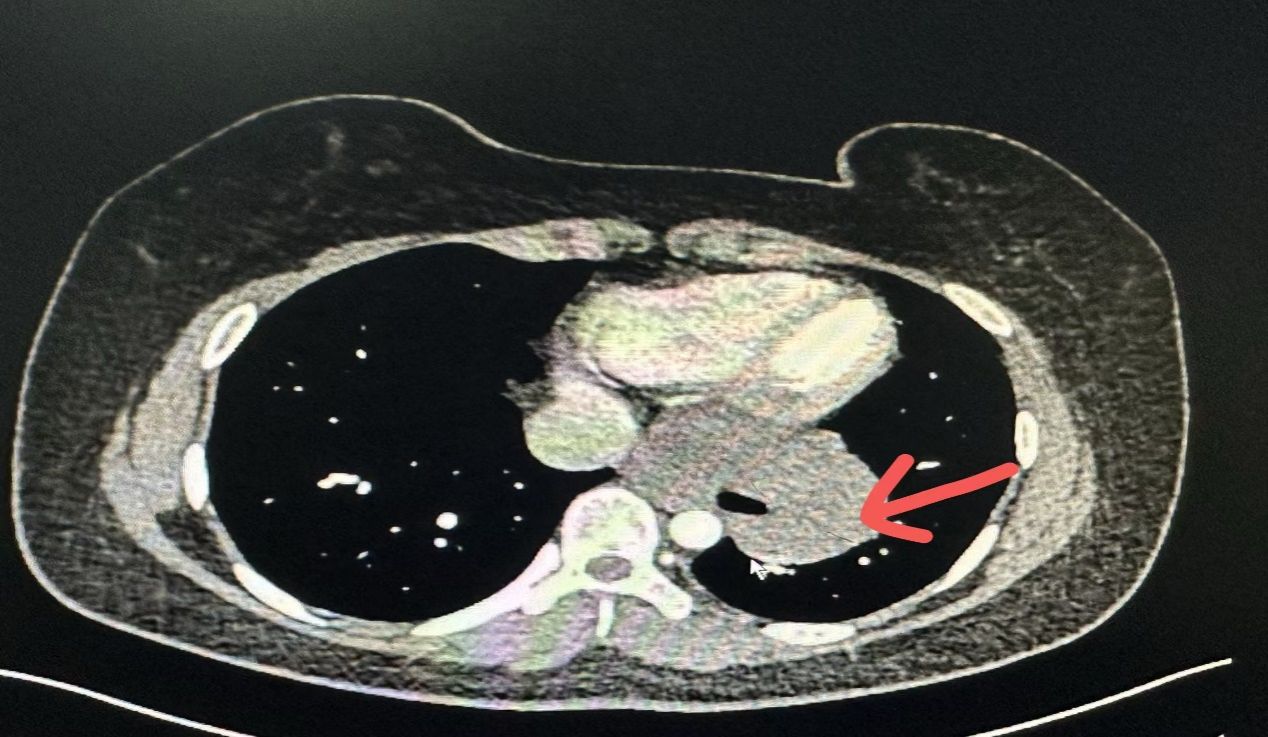

在2024年10月21 日,姜建涛主任医师、李建忠副主任、赵丹文医师为小张实施了手术治疗,术中先尝试胸腔镜手术,腔镜下可见食管下段至贲门巨大隆起性病变,姜主任评估后认为腔镜下操作困难大,遂将操作孔延长至5cm行手术,术中发现肿瘤环食管周生长,完整剥除及其困难,但考虑小张年轻,未避免切除食管而对小张以后的生活造成影响,姜主任团队仔细操作,尽可能为小张保住食管,在姜主任及其团队的精心操作下,手术顺利,手术仅历时一个多小时,便将肿瘤完整剥除,剥除下来的肿瘤长径达到了快13cm,试水检查食管粘膜未损伤。在术后第一天查房的时候小张已经能下地活动了,激动的拉着姜主任的手,感谢姜主任为她成功实施手术并保住了食管,感叹姜主任的高超技艺,现小张一切恢复顺利,已康复出院。